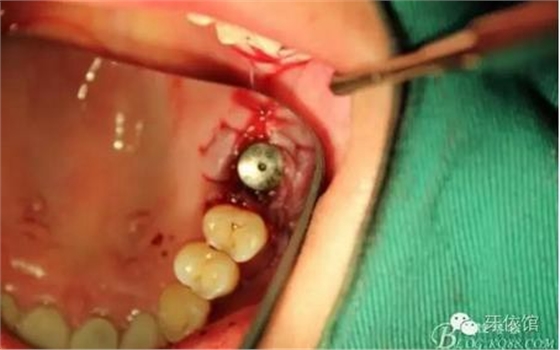

間隔上備的洞內(nèi)可以看到上頜竇膜

植入骨粉

植入植體

縫合

術后x光片,右上6直接上愈合基臺,但未完全就位,右下7手術過程略